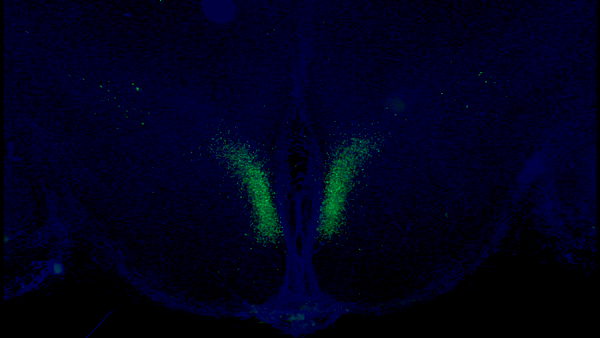

Výskum naznačuje, že keď sa toto spojenie s vekom zhoršuje, môže to viesť k rôznym zdravotným problémom súvisiacim so starnutím. Štúdia, ktorá bola uverejnená v časopise Cell Metabolism, zlepšuje naše chápanie starnutia a vyvoláva nádej na budúcu liečbu, ktorá by mohla udržať túto spätnú väzbu neporušenú a spomaliť starnutie. Vedci skúmali špecifické neuróny v časti mozgu nazývanej hypotalamus.

Zdroj Foto: Kyohei Tokizane

Hlavný autor štúdie Shin-ichiro Imai uviedol, že táto práca odhalila spôsob, ako oddialiť starnutie a predĺžiť zdravý život myší pomocou manipulácie mozgu. Hlavné zapojené bunky sa nachádzajú v dorzomediálnom hypotalame a produkujú proteín s názvom Ppp1r17. Ten udržiava neuróny aktívne a ovplyvňuje sympatický nervový systém, ktorý spúšťa reakcie, ako je zvýšená srdcová frekvencia.